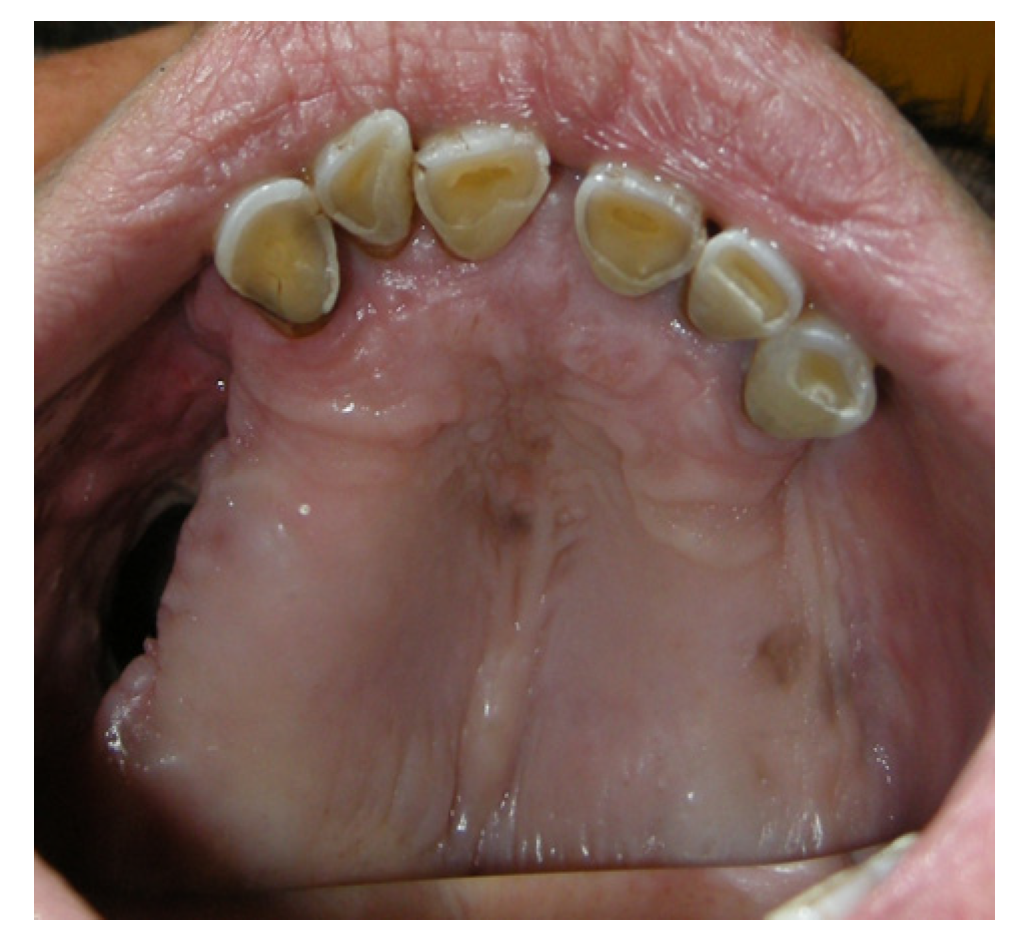

3.1.4. Case 4: P.M.A.

| P.M.A | X | * | 5 | 5 |